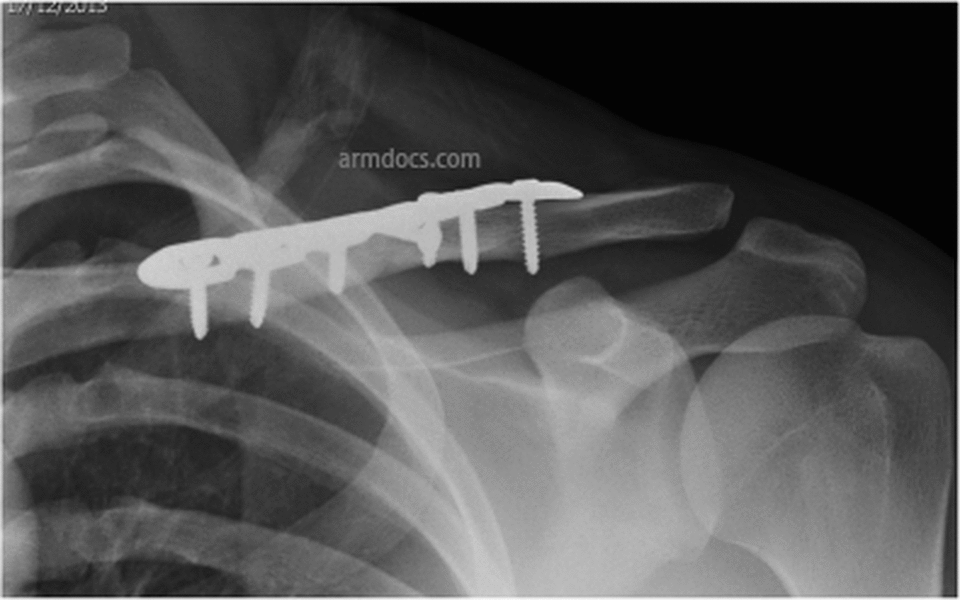

Clavicle Fracture Plate Fixation Arm Docs

From www.armdocs.com